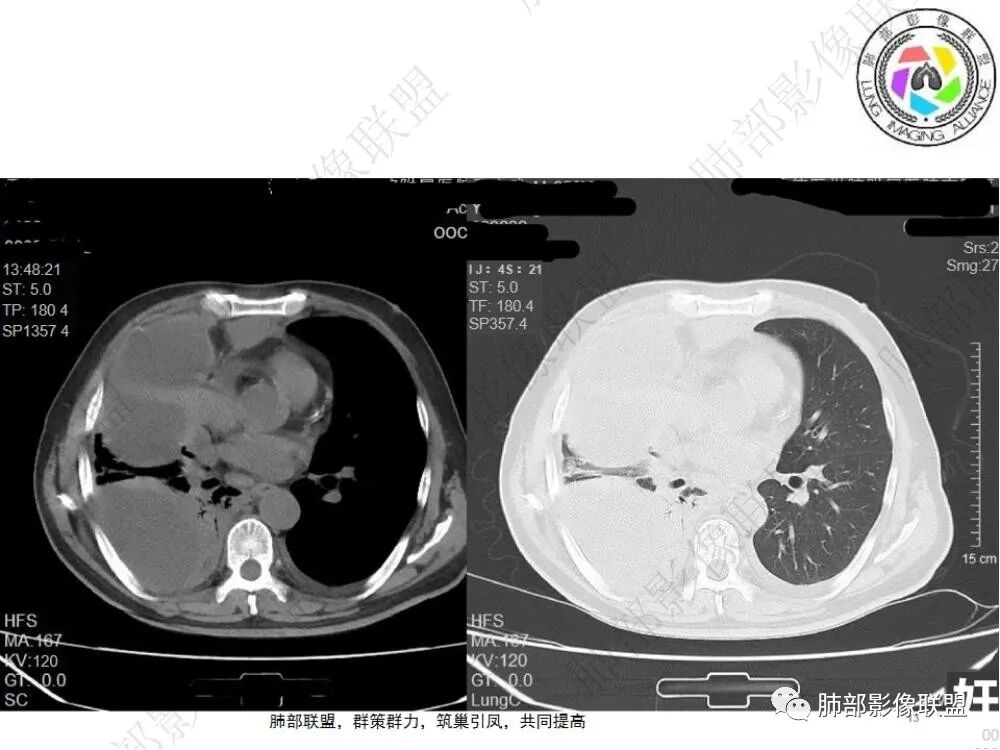

2.影像显示右肺上叶后段及右肺下叶较大范围实性密度为主片状影,边界可分辨,密度较均匀,隐约见小范围低密度(可疑液化区),未见钙化及气囊影。

4.右侧胸腔积液,多包裹局限。

6.一周后复查变化较为明显。肺部实变影有所吸收,但胸腔积液增加明显,包裹于侧胸壁、纵隔旁及叶间裂。注意右肺下叶因积液推压明显(可惜未能提供薄层图片及矢状位图片)。